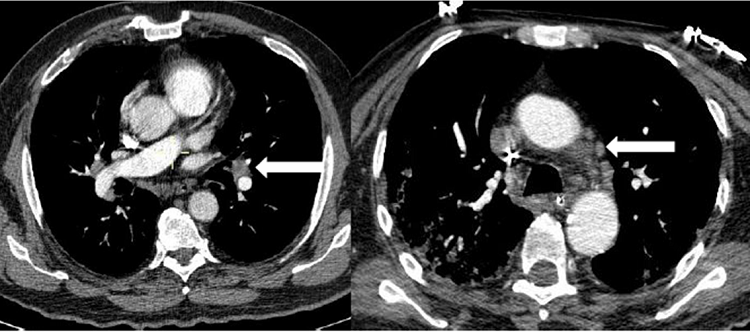

Todos los pacientes de la serie tenían hipoxia y aumento de las cifras de Dímero D con normalización en la cifra de otros parámetros típicamente alterados en esta enfermedad. De los ocho pacientes con TEP solo en dos había afectación múltiple y en ramas principales y lobares (Figura 1). En uno de los dos casos días después se confirmó la existencia de una extensa trombosis de las venas iliacas y femoral derecha como causa del TEP (Figura 2). En los otros seis casos el trombo era único y en ramas de pequeño calibre (Figura 3). En uno de los pacientes el trombo afectaba a la vena pulmonar superior izqda (Figura 4).

En la mayoría de los casos en que se vio enfermedad tromboembólica la enfermedad pulmonar era grave desde el punto de vista de la imagen,seis casos (Figura 5), en otro era moderado-grave y en un tercer paciente no había evidencia de afectación pulmonar, el paciente estaba diagnosticado de silicosis pulmonar (Figura 6) y tenía antecedentes de una neoplasia de páncreas irresecable a tratamiento con quimioterapia con fiebre y PCR positiva para COVID-19. Cuatro de los 8 pacientes con TEP tenían enfermedad muy evolucionada y grave con respiración asistida e ingreso en la UCI. Todos los pacientes tenían adenopatías mediastínicas lo que podría traducir un estado de gran inflamación (Figura 7) que podría explicar la cifra alta de Dímero D en los casos en que no existía enfermedad tromboembólica.